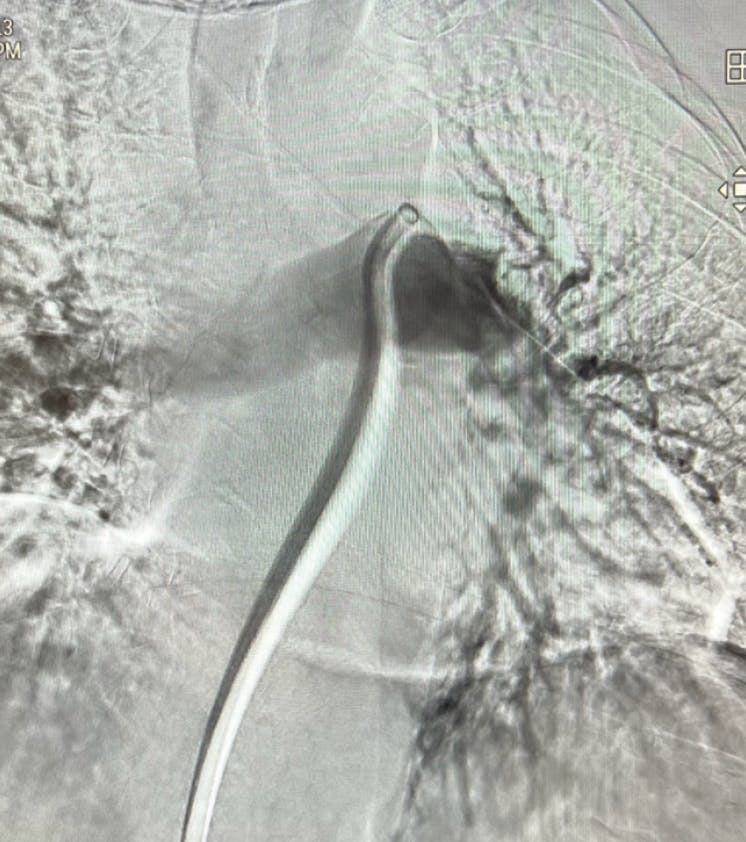

Figure 1. Right lobe initial angiogram.

Figure 2. Left lobe initial angiogram.

A man in his mid-70s presented with a bilateral PE. The patient has a history of both deep vein thrombosis (DVT) and PE occurring 7 years ago. Initial diagnostic testing revealed a troponin of 295.9 mg/mL, B-type natriuretic peptide (BNP) of 70 pg/mL, and a hemoglobin of 13.5 g/dL. The PE was discovered via CT from an external facility; the patient was then transferred to our practice the same day (Figure 1 and Figure 2). The patient presented with a BP of 141/97 mm Hg, HR of 80 bpm, and oxygen saturation of 95% on 40 L/min on a 50% non-rebreather.